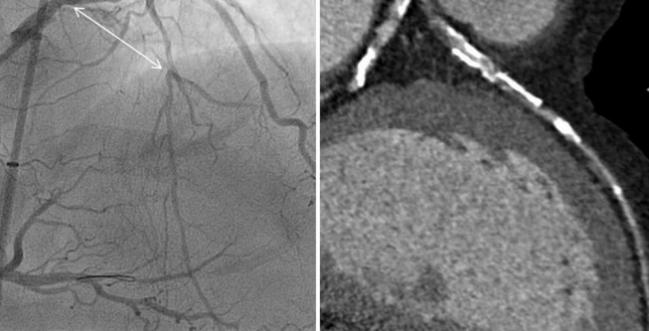

Photo Credit: Adapted from Jaffer F. CT for Procedural Planning in CTO and Complex Coronary Interventions. Presented at: TCT 2016. November 1, 2016. Washington, DC.

“Although coronary CTA effectively rules out coronary disease, it is limited in its ability to assess the hemodynamic importance of angiographic lesions,” the authors explain, noting that the addition of MPI to CTA might address that shortcoming and ultimately reduce the use of invasive angiography in patients who do not have hemodynamically significant disease.

The CT protocol started with a calcium scan, followed by CTA if any calcium was detected or if patients had a greater than 80% pretest probability of CAD in the absence of calcium. Patients with more than 50% stenosis on CTA underwent CT MPI. When substantial myocardial ischemia was detected, patients were referred for invasive angiography, with the rest treated with medical therapy.